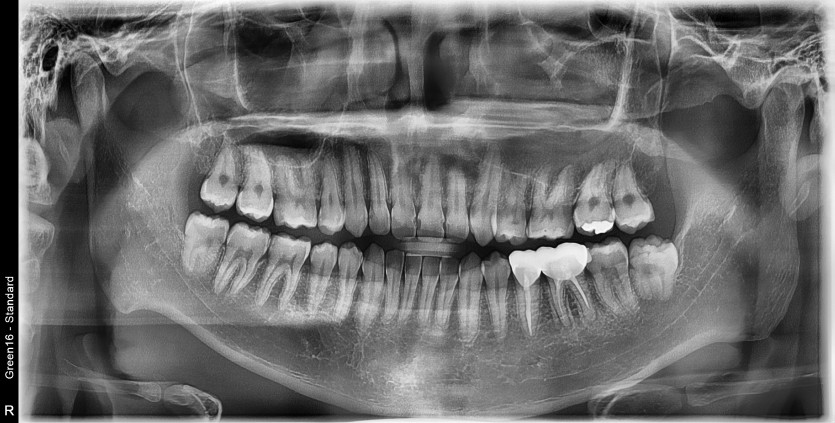

#18,48 사랑니 발치

구강외과 전문의가 당일발치했습니다.